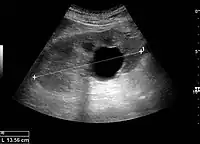

Figure 5. Simple renal cyst with posterior enhancement in an adult kidney. Measurement of kidney length on the US image is illustrated by '+' and a dashed line.[1]